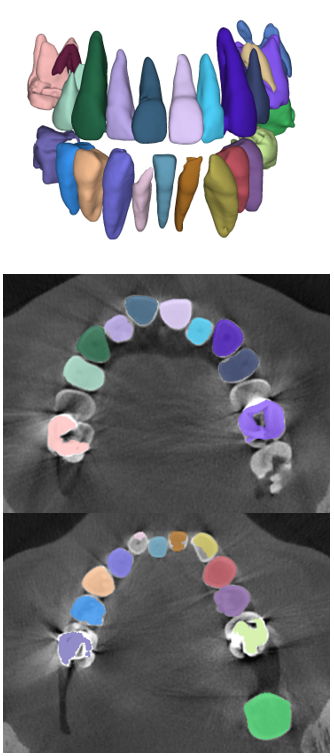

The manual seeded level-set methods [6, 7] demonstrate inferior performances while segmenting teeth with predominant metal artifacts (Table II). The energy-based (i.e., level-set function) algorithmic approach failed while defining an optimum stopping criterion (Fig. 12b). The AJI measures for level-set methods are omitted because the box detectors do not exist in the level-set-based methods. In particular, the low precision and sensitivity values indicate that level-set methods have over-segmented or under-segmented the teeth in many cases (Figs. 12b and 13a). The accuracies of the Mask-RCNN [17] and ToothNet [11] showed comparable performance to the level-set-based methods. The instance segmentation framework successfully detected and segmented the teeth automatically. However, it failed to detect all the teeth regions accurately, which resulted in a degradation of the segmentation performance. Moreover, the performance of the segmentation itself also showed low accuracy owing to the metal artifacts (Figs. 12c and 12d). Figure 13 illustrates the more severe conditions of metal artifacts. The performance of the detection and segmentation processes significantly degraded in ToothNet [11] (Fig. 13b) and Mask-RCNN [17] (Fig. 13c). Conversely, our proposed method outperformed the other state-of-the-art methods (Figs. 12e and 13d); further, the comparison between the PA- and non-PA-based results also demonstrated that the employment of a PA detector significantly improved the proposed architecture (Table II). The superior AJI value clearly shows that successful detection improved the overall performance.